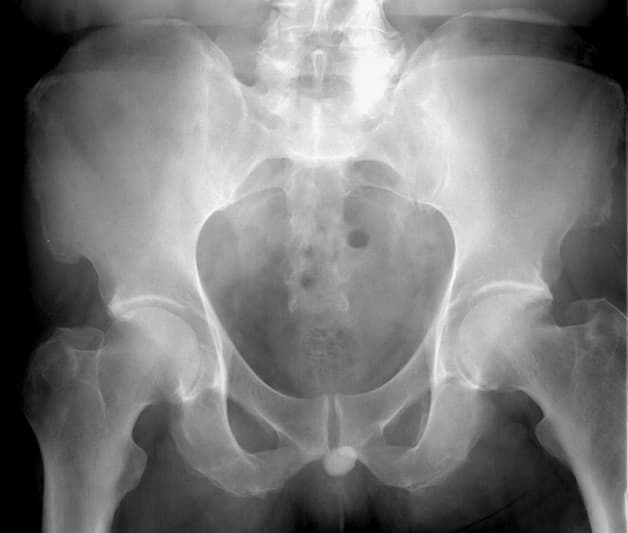

– Chụp X-ray hệ tiết niệu

Chụp X-quang cho giúp xác định vị trí của sỏi